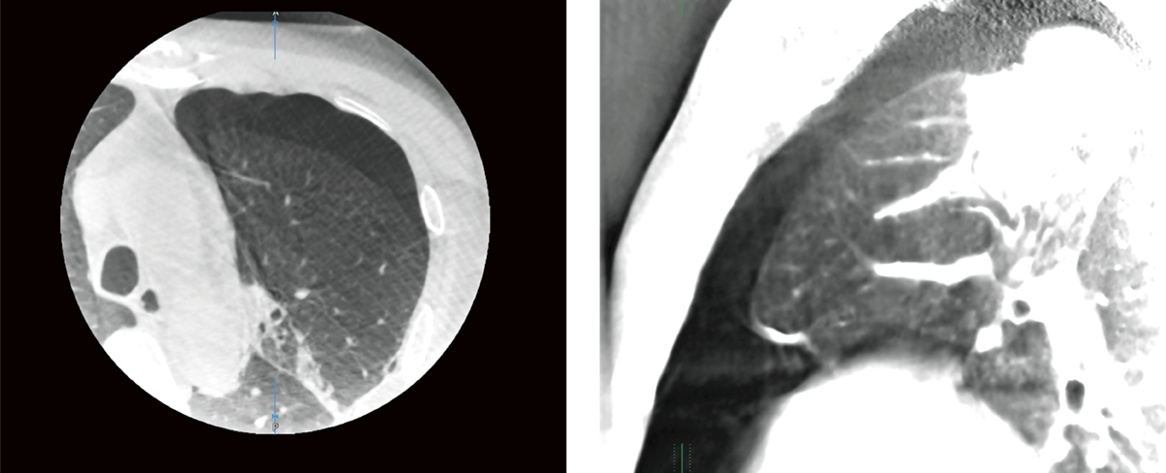

Alpha CT (Cone Beam CT)

Alpha CT основується на даних, отриманих під час обертальних рухів C-арки. Рекоструйований 3D об’єм можна перенести на робочу станцію (AWS) для перегляду. Об’ємна візуалізація (VR), проекція максимальної інтенсивності (MIP), мультипланарна реконструкція (MPR), осьовий, сагітальний та корональний вигляд можуть використовуватися для візуалізації цільової анатомії/патології, таких як придаток лівого передсердя, пневмо- або гемотораксу або перикардіального випоту.

MPR зображення з Alpha CT легенів показує пневмоторакс після біопсії